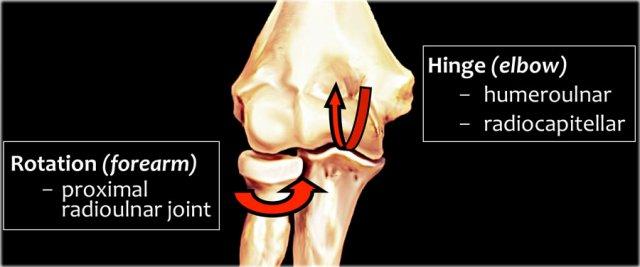

Elbow Mechanics

Khuỷu tay đóng vai trò như một khớp bản lề khi chúng ta xem xét khớp cánh tay-trụ và khớp quay-mỏm cầu.

Khớp còn lại là khớp quay trụ gần với chuyển động xoay cho phép sấp và ngửa.